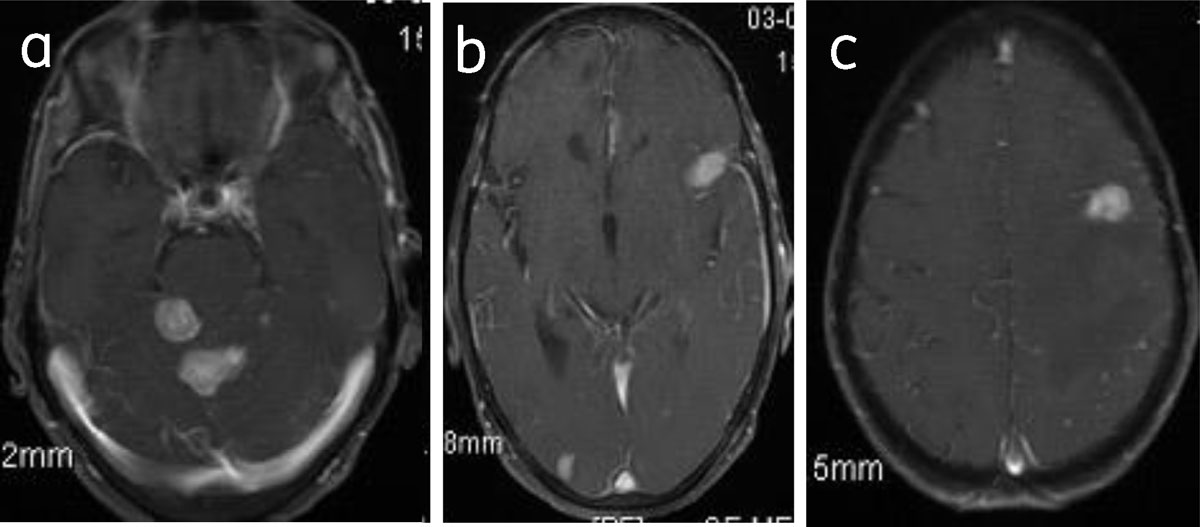

Figure 15

Meningiomatosis: Axial post-contrast (a, b, c) images show multiple enhancing meningiomas.